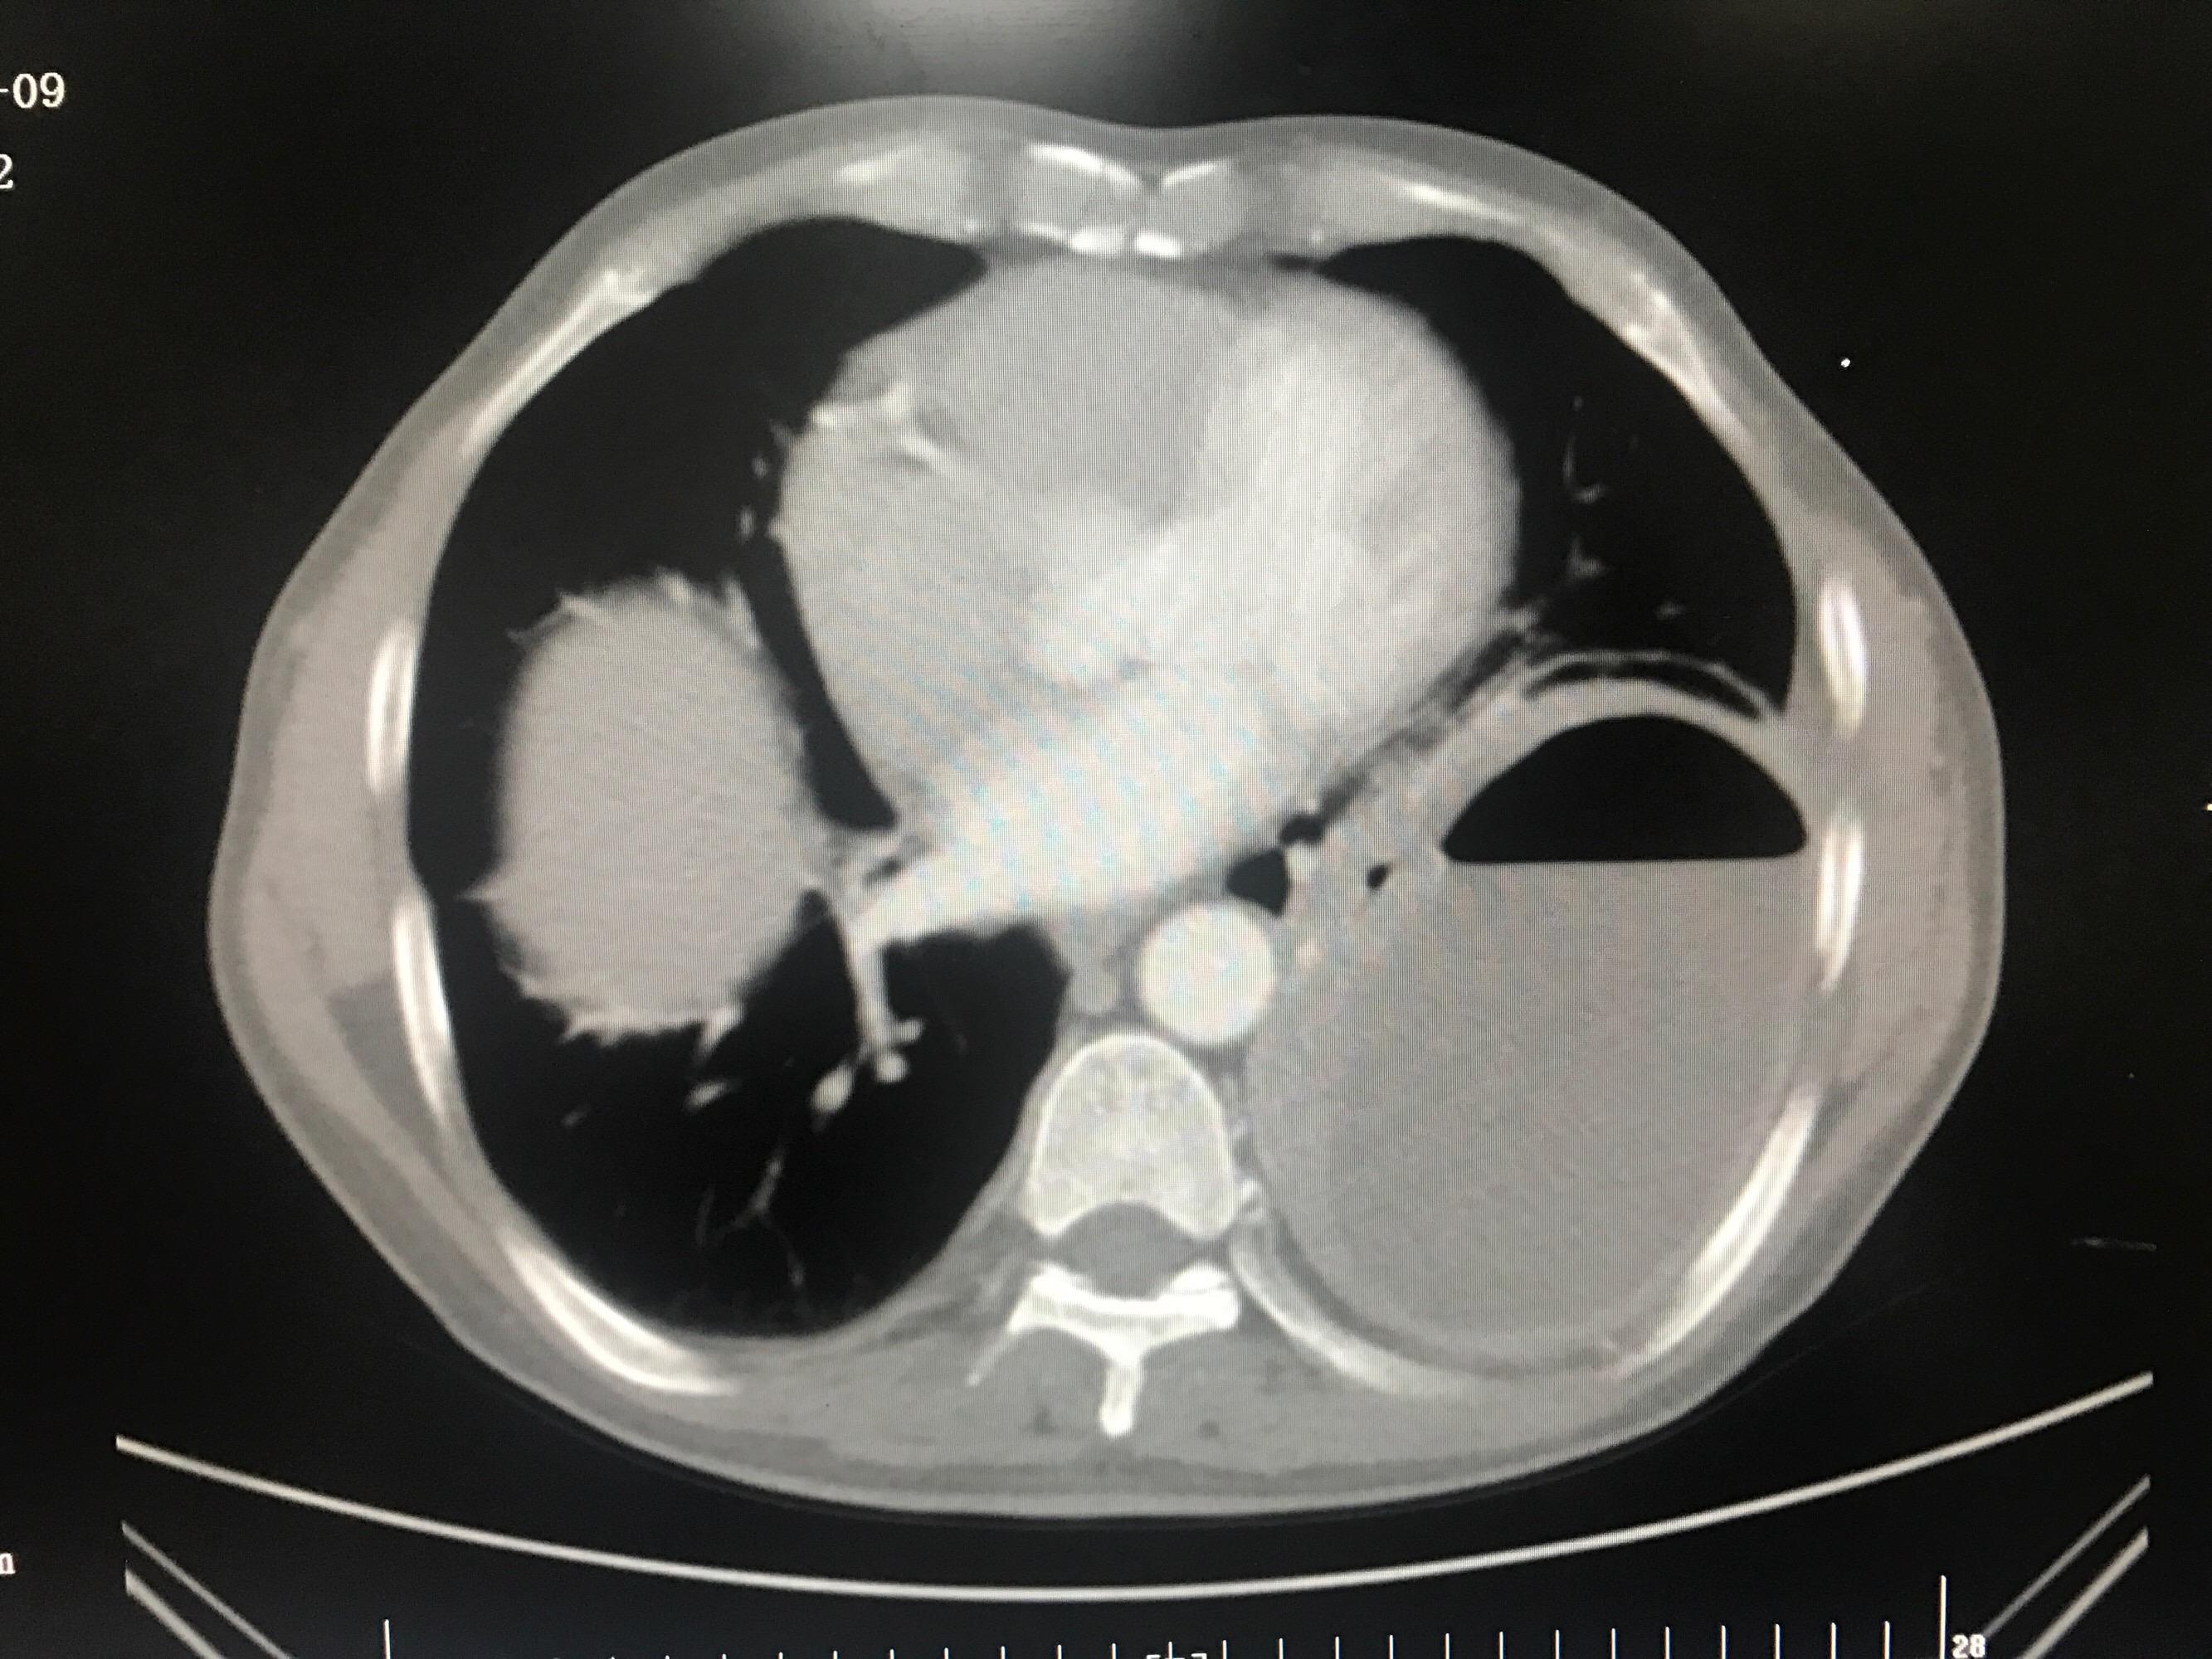

ct 影像显示肺部存在一个大厚壁空洞,大小 62*44mm,需要鉴别脓肿伴

一个肺脓肿患者,差点被误诊为肺癌 这个病人50岁,咳嗽,咳痰四五天了